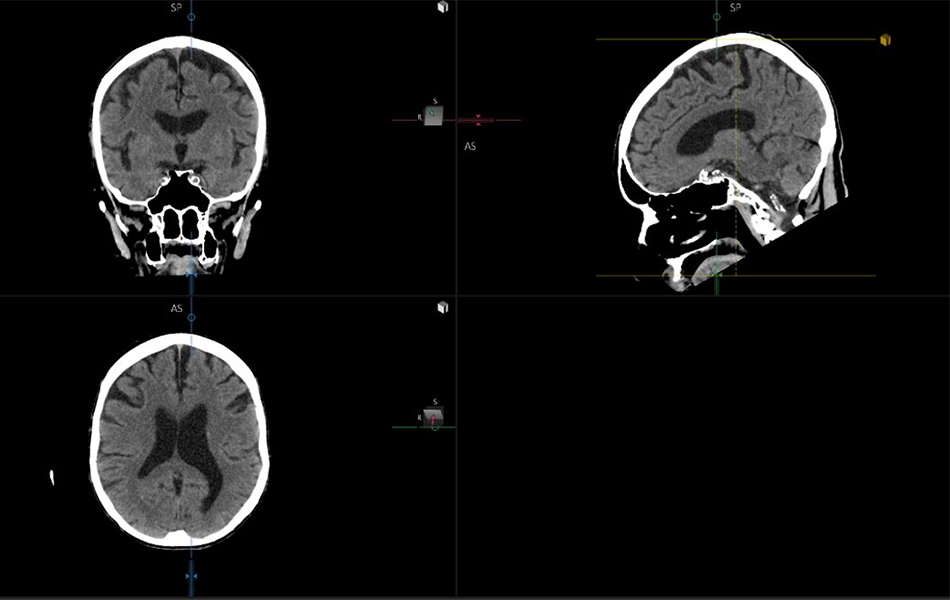

Auto MPR Brain (7.15.8)

The Auto MPR Brain software package utilizes anticipatory processing, or Just-In-Time (JIT) processing, for CT brain images. Auto MPR Brain receives volumetric CT brain image data and automatically aligns the multiplanar reformatted images into a standard anatomical position based on the OM line.